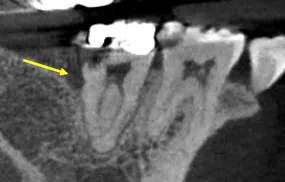

C-shaped canals occur in approximately 30-45% of mandibular second molars in certain populations, but they're rarely encountered by general dentists because the anatomical variation isn't visible on standard radiographs. This patient's CBCT revealed a Type I C-configuration—a continuous ribbon of pulp tissue connecting what would normally be separate mesial and distal canals.

Standard treatment protocols don't work for C-shaped anatomy. You cannot simply "find the canals" and file them independently because there are no discrete canals—just a continuous C-shaped space with isthmus connections throughout the entire root length.

• Access Modification: Trapezoidal cavity instead of traditional triangular to expose entire C-configuration

• Circumferential Filing: Rasping motion along the inner and outer walls of the C-shape rather than traditional filing

• Thermoplasticized Obturation: Warm vertical compaction to fill irregular three-dimensional anatomy

• Multiple Cone Technique: Several gutta-percha points placed to fill the ribbon-like space

The procedure took 90 minutes. The patient's severe pain resolved immediately after treatment.